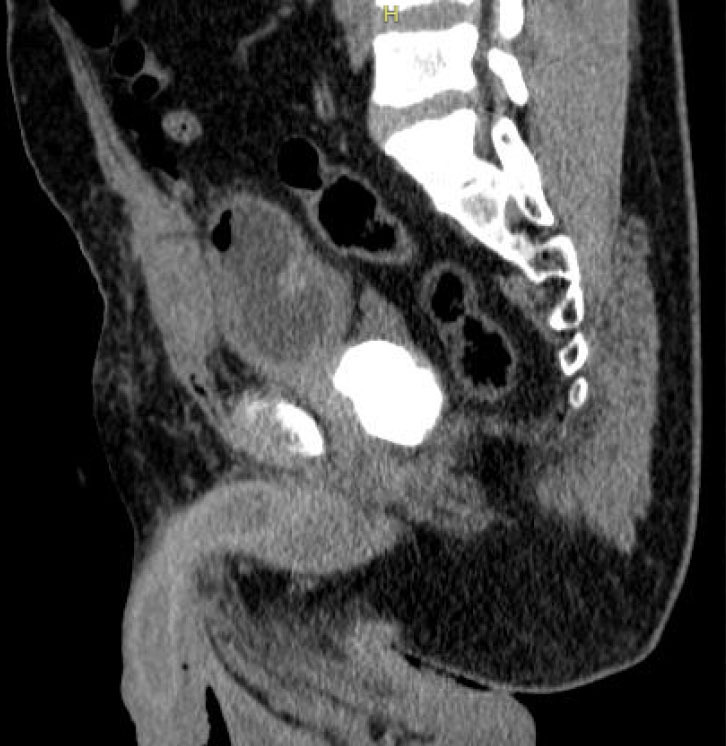

Case description: A 34-year-old male was admitted to the emergency service of a university hospital reporting dysuria and pain in the hypogastrium with a 4-day history. The patient reported that the pain sometimes irradiated to the left flank, accompanied by micturition effort, a weak urinary stream, pollakiuria, and urine output with a crystal appearance. The clinical history revealed urinary difficulty since 10 years of age. The patient was submitted to radiological investigation. Pelvic computed tomography revealed a voluminous calculus with slightly lobulated contours in the intravesical topography in the interior of the prostatic urethra. Urethrocystography revealed a prostatic calculus and the tapered passage of contrast through the prostatic urethra. After the diagnosis, the rectal examination confirmed the presence of a hardened calculous mass in the prostatic topography. Considering the complementary evaluation of the patient, perineal prostatotomy was planned. Prostatotomy was performed longitudinally in the prostatic capsule for the removal of the calculus after its release by dissection.